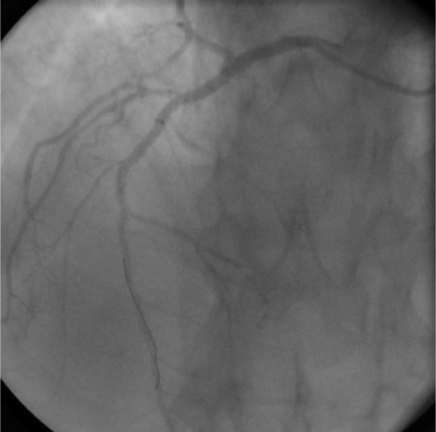

A 55-year old man was transferred from one of our referring hospitals with early post infarct unstable angina, having chest pain in the right side of the chest radiating to the right shoulder and the back, following an anterior ST-elevation myocardial infarction for which he had received thrombolytic therapy. He was a known case of dextrocardia with Kartagener syndrome, diabetic and smoker. Physical examination was unremarkable except for findings consistent with dextrocardia. Apart from raised troponine-I and blood sugar, his routine laboratory tests were within normal values. 12-lead Electrocardiogram (ECG) showed a negative P wave lead-I and aVL and positive P and R waves in aVR together with Q waves in inferior leads. Reversed chest leads showed QS in V1-V3 with ST depression in V4-V6 associated with deep T wave inversion. Chest X-ray revealed dextrocardia with a right-sided aortic knob as well as gastric bubble. Echocardiography revealed left ventricle ejection fraction of 40% with hypokineses correspondent with ischemia in left anterior descending artery (LAD) territories and no significant valve disease. Cardiac catheterization was performed via the right radial artery using mirror-image views and standard Judkins catheters. A 5 French (Fr) angulated pigtail catheter was through the right-sided aortic knob into the left ventricle. The 300 left anterior oblique (LAO) ventriculogram (Figure 1) showed anterior wall hypokinesia and severe hypokises/akineses of the apex and the inferior wall with an ejection fraction of 40%. The ostium of the right coronary artery (RCA) was easily engaged by gentle counterclockwise rotation and slightly withdrawal of a 5 Fr Judkins right 4 cm (JR4) diagnostic catheter in right-anterior-oblique (RAO) and RAO-cranial views showed 100% lesion at mid-RCA segment (Figure 2). The ostium of the left main coronary artery was also cannulated using a 5 Fr Judkins left 4-cm (JL4) diagnostic catheter in a RAO view. The selective left coronary angiogram revealed a>70% tubular stenosis in the middle segment of LAD artery and a patent left circumflex (LCX) artery (Figure 3). Adhoc-PCI to LAD was performed with the use of 5 Fr JL 3.5 guide catheter and a 0.014” balanced middleweight (BMW) guide wire. Two overlapping drug-eluting stents (Xience Prime 2.5x28mm and Promus Element 2.25x12mm) were directly deployed at the site of the lesion in the middle segment of the LAD artery with good angiographic result (Figure 4). The patient experienced an uneventful post-PCI course and was discharged on the following day. He was free of angina on clinical follow-up.

Figure 3 Left coronary angiogram in postero-anterior/cranial 40˚ view showing significant lesion in mid left anterior descending artery (LAD). The anatomy is mirror image to the same view in normal case.